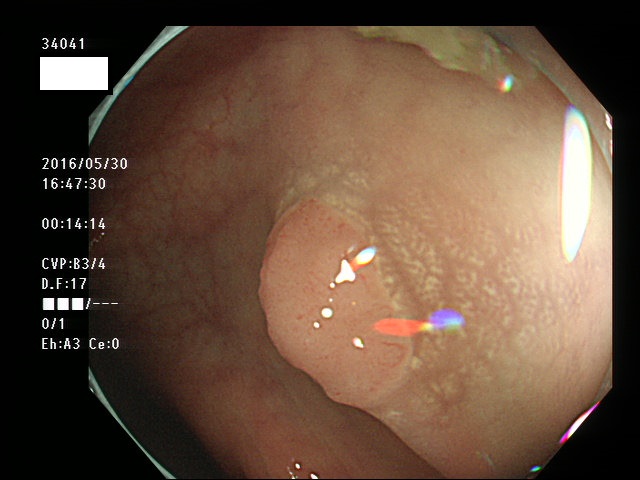

上記100名より抽出した平坦・陥凹型腺腫(=癌化の危険が高いが見落としやすい病変)の内視鏡写真